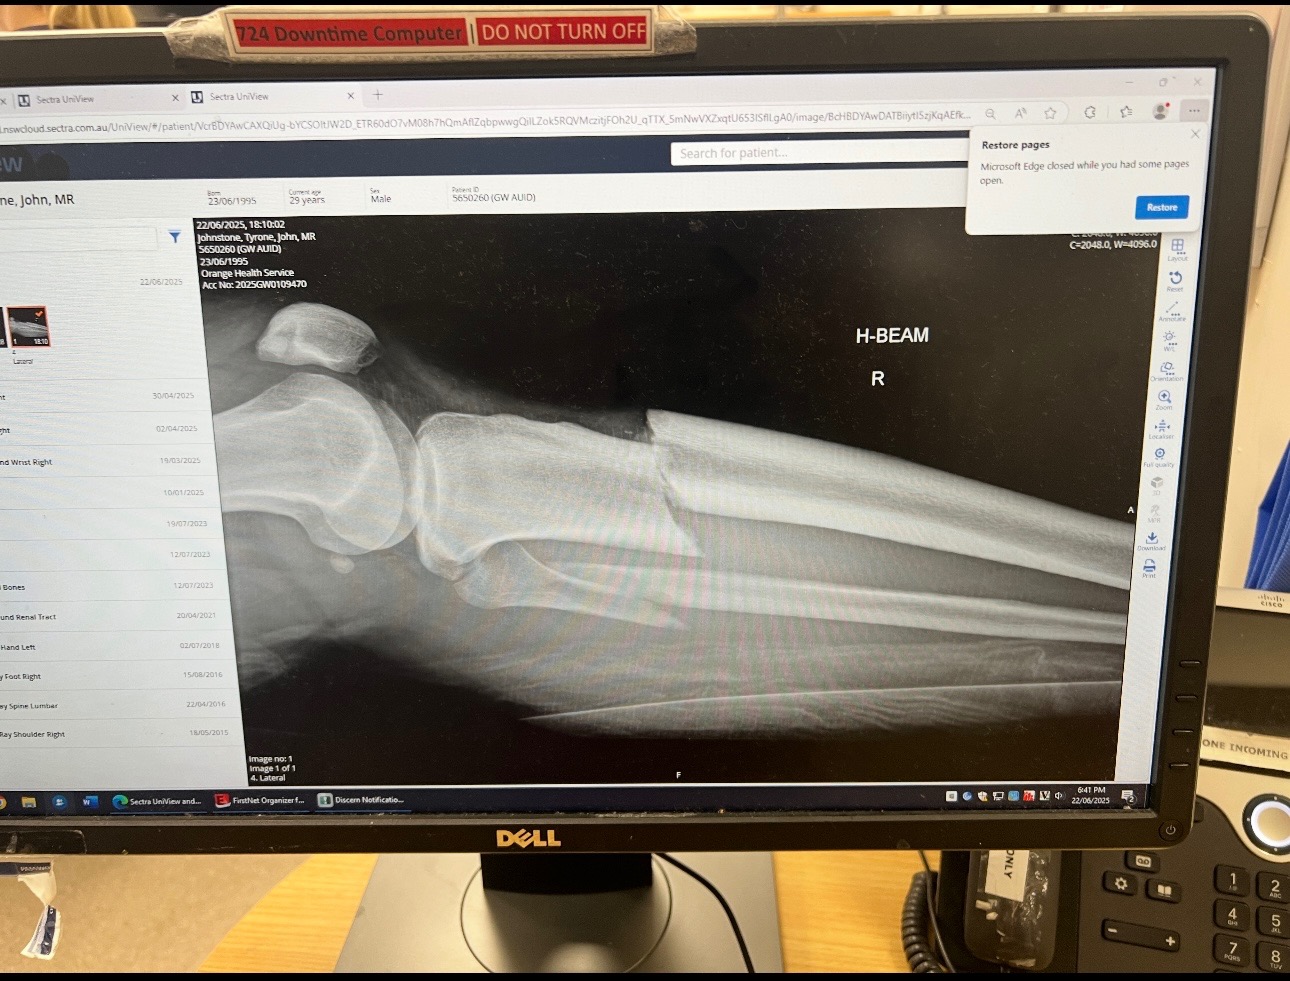

Tj was playing Rugby League for Condobolin Rams on Sunday the 22nd when he was involved in a nasty tackle, leaving him with a broken leg. Both Tib & Fib bones are broken, leaving Tj unable to work & provide for his little family.